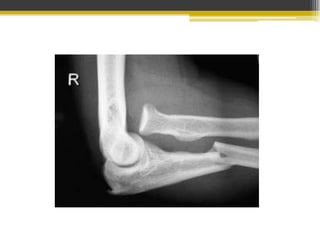

Fractura supracondílea

• Radiología: Proyección lateral del codo

inclinado y desviado hacia atrás.

•

• Estrés en valgo

• Traumatismo directo

• Tratamiento ortopédico